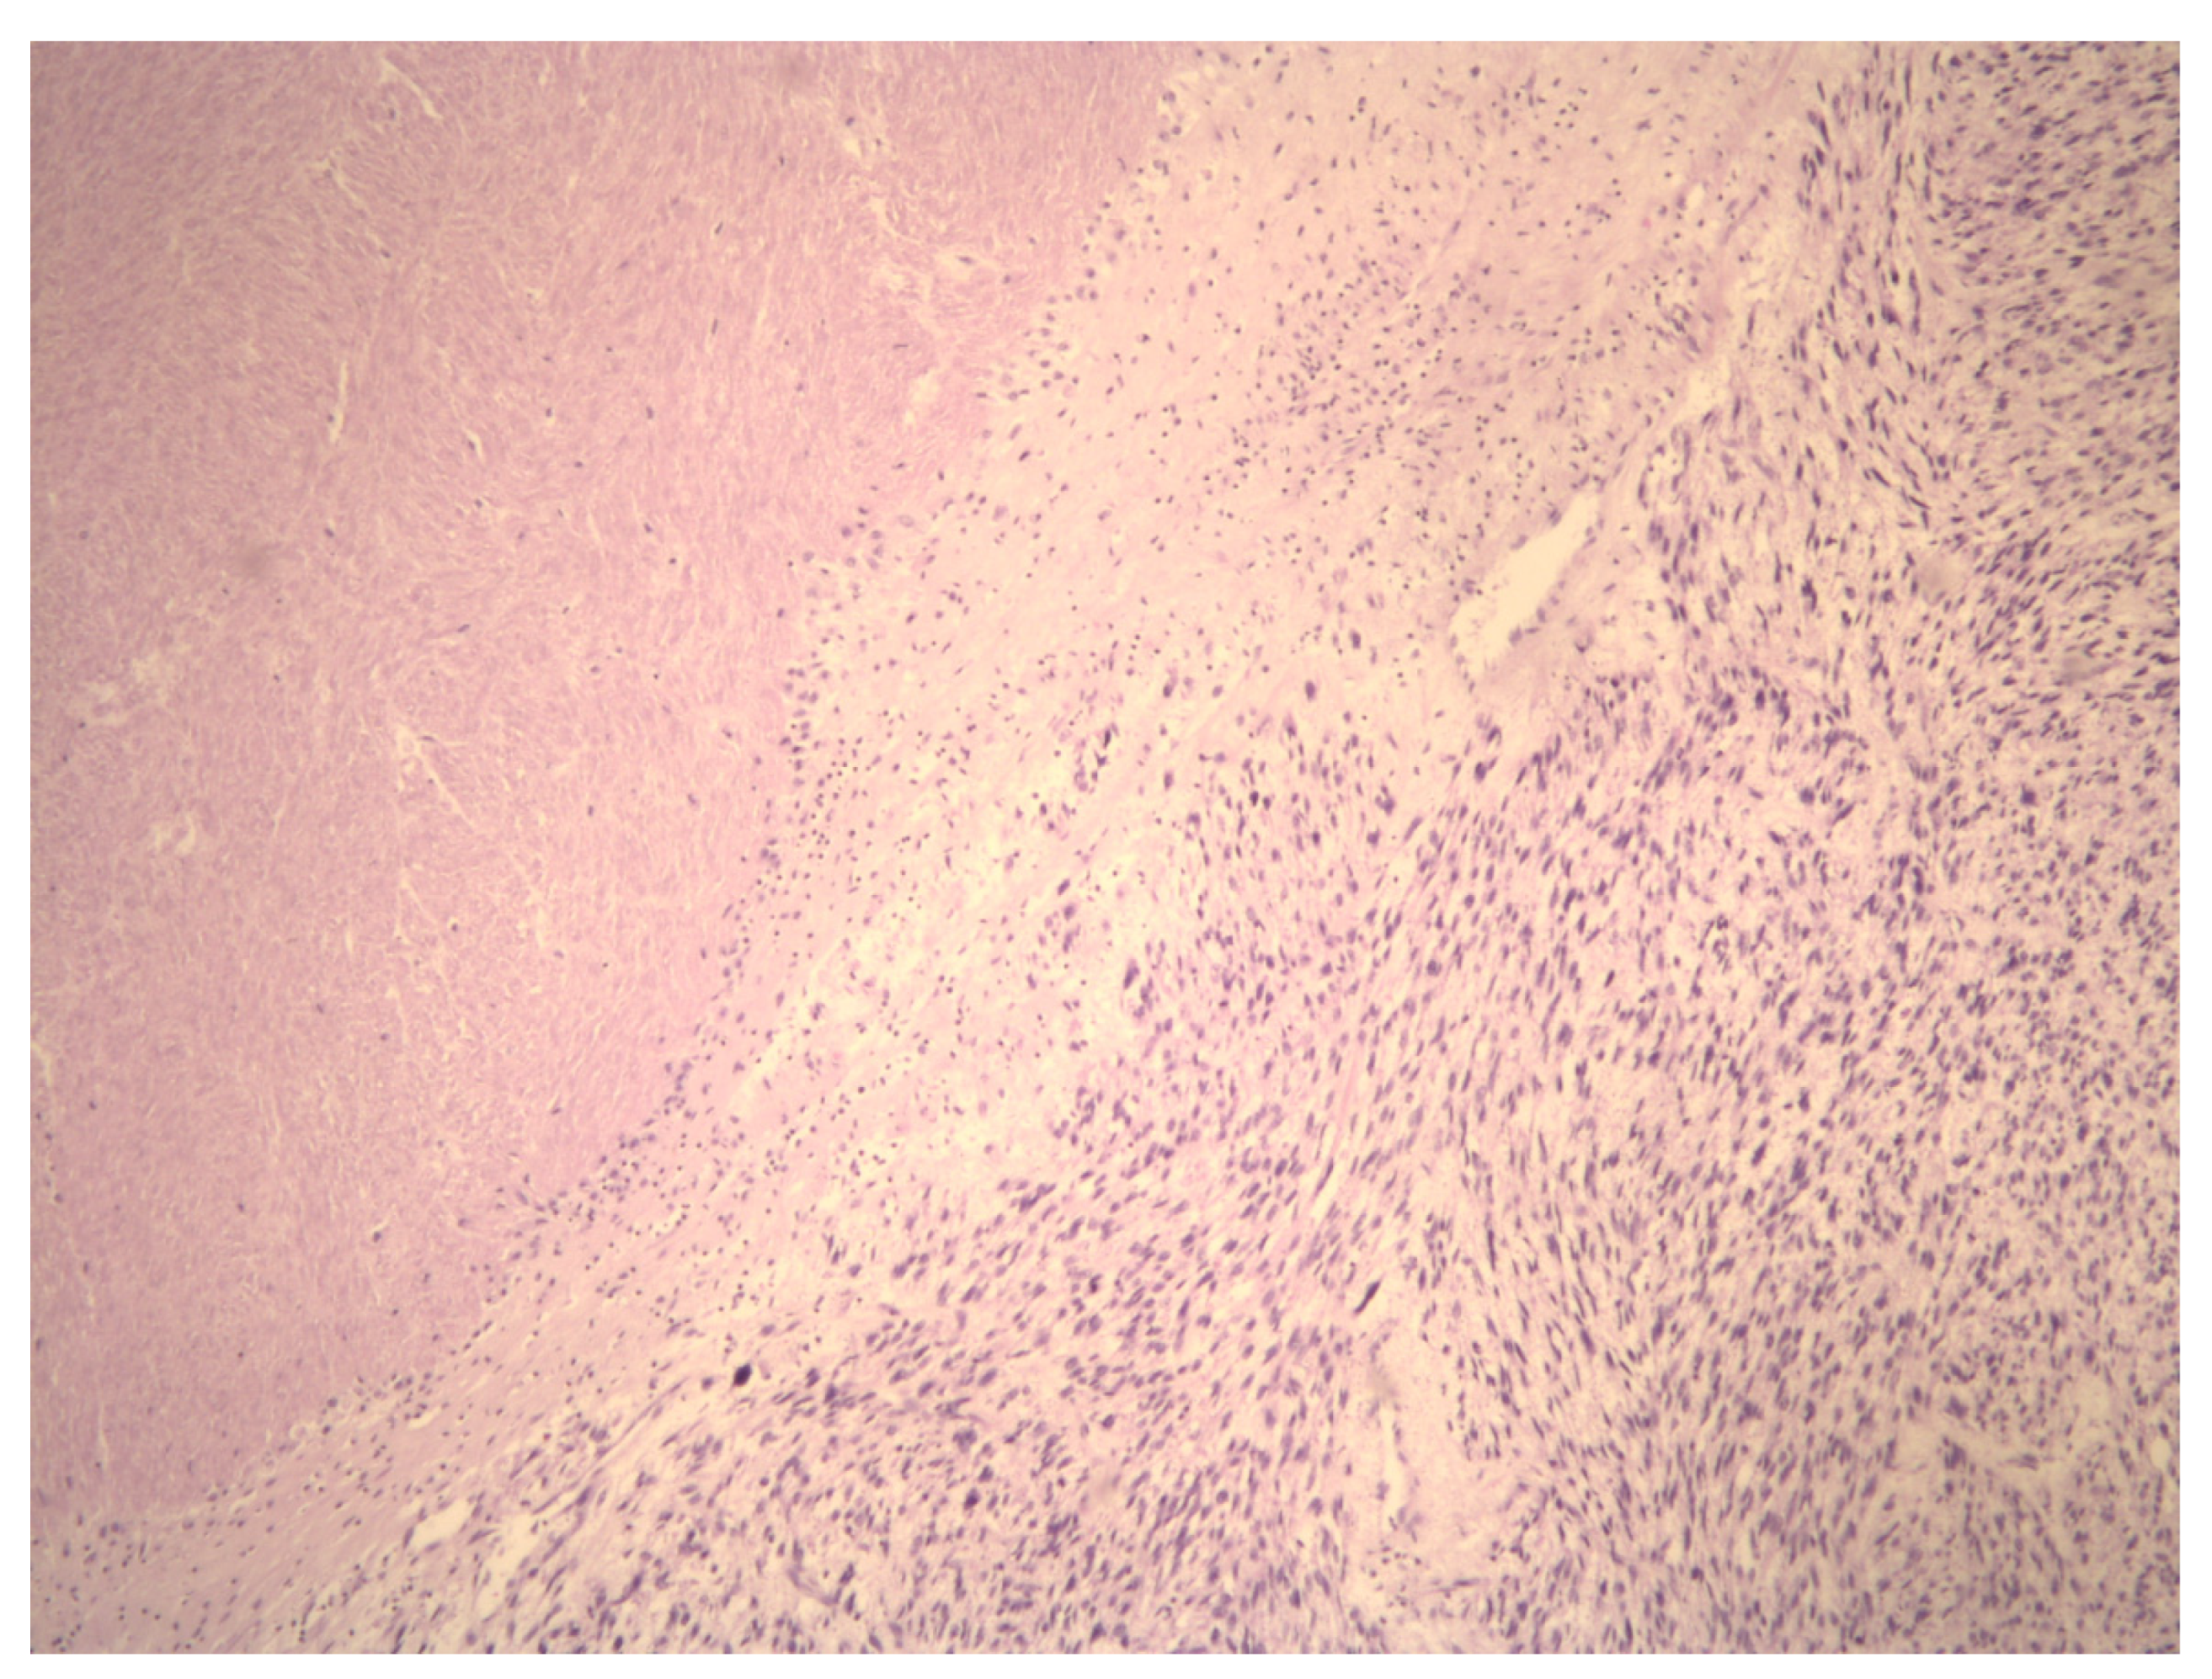

- Zhang, Q.; Kanis, M.J.; Ubago, J.; Liu, D.; Scholtens, D.M.; Strohl, A.E.; Lurain, J.R.; Shahabi, S.; Kong, B.; Wei, J.J. The selected biomarker analysis in 5 types of uterine smooth muscle tumors. Hum. Pathol. 2018, 76, 17–27. [Google Scholar] [CrossRef] [PubMed]